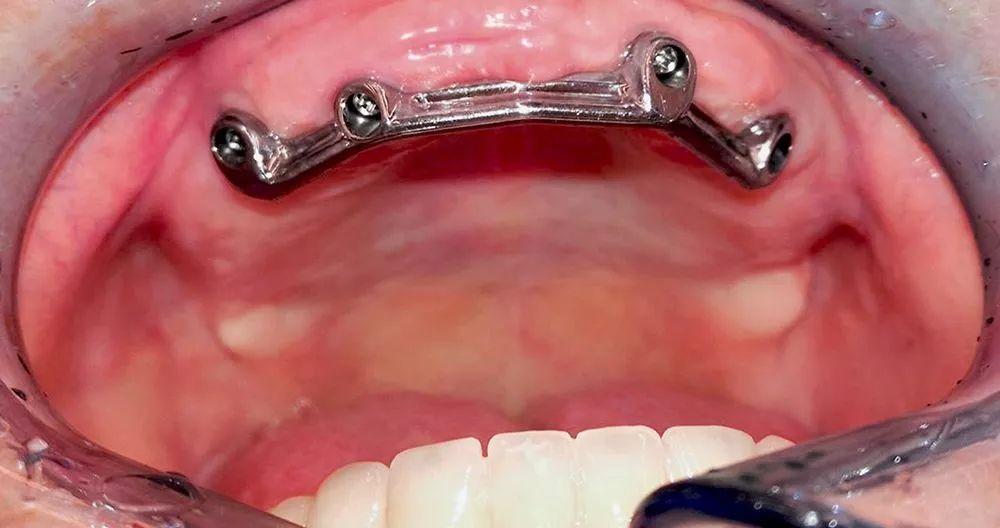

種植手術(shù)導(dǎo)板(半口/局部):

種植手術(shù)導(dǎo)板按照使用顆數(shù)收費,局部和半口報價不同。根據(jù)CBCT數(shù)據(jù)和石膏模型進(jìn)行數(shù)字化3D種植方案,及種植手術(shù)導(dǎo)板設(shè)計。通過3D打印技術(shù)制作外科手術(shù)導(dǎo)板,同時將引導(dǎo)型套筒固定在導(dǎo)板中。

種植手術(shù)導(dǎo)板可以減小創(chuàng)口,增加位置空間性,減少手術(shù)風(fēng)險。